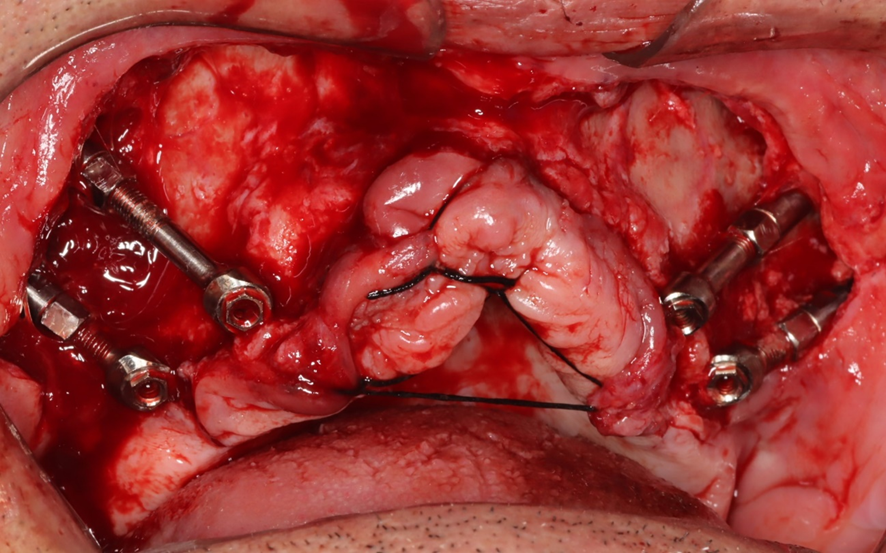

Caso 1 – Híbrido: dois Pilares Z e dois implantes convencionais

Caso 2 – Protocolo com quatro fixações

O torque na montagem durante a instalação dos pilares em boca será de 30N no parafuso do Cone Morse e 80N na porca que une os segmentos B e C. (Técnica Facco).

O posicionamento, junto ao rebordo alveolar, das plataformas dos Pilares Z, deverá ser aproximadamente próximo ao 16/26 para distais e próximo ao 12/21 para mesiais, configurando assim o polígono de Roy.